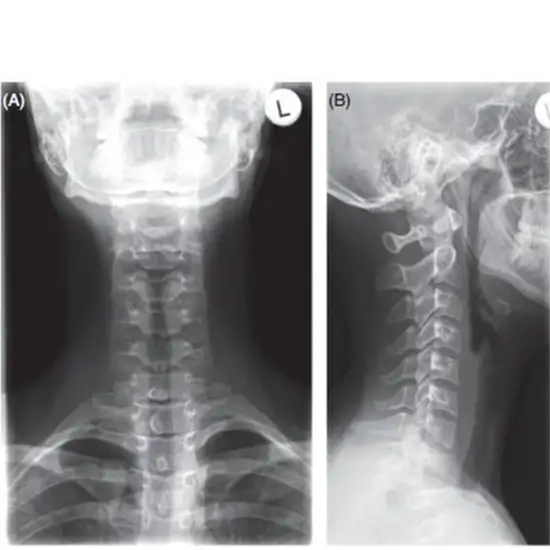

X-Ray Cervical Spine AP & Lateral View

AP and LAT X-rays of the cervical spine View test sees the first seven vertebrae (C1–C7). This test lets the doctor see the intervertebral discs and the skin and muscles around them.

This test is given to find the cause of neck pain, check for damage to the spine's bones, look for tumors or infections of the spine, and look for problems with the discs.